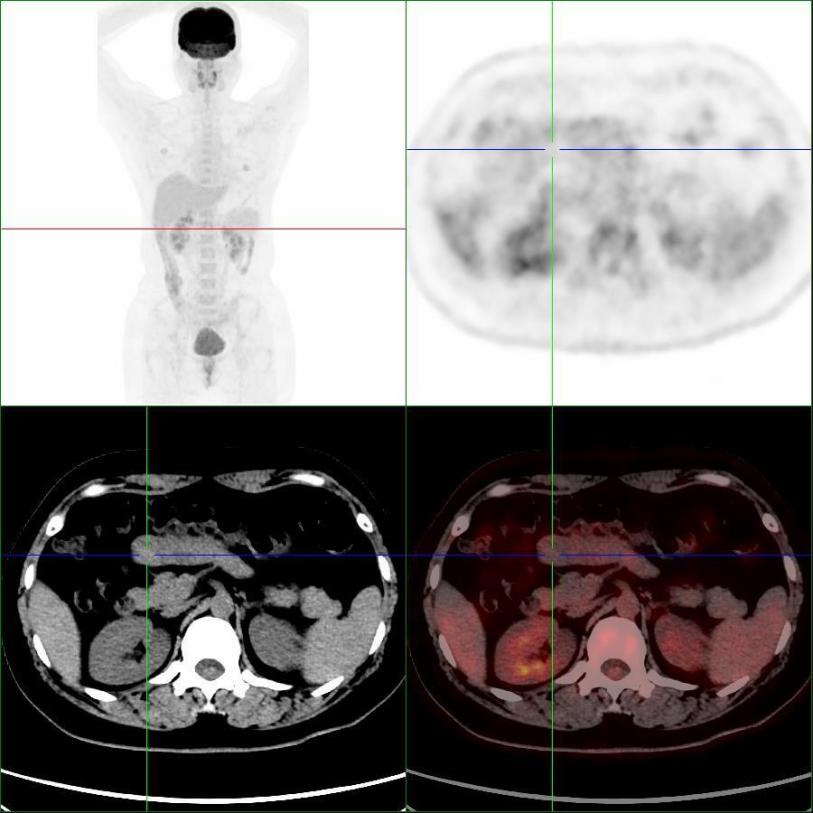

患者完善PET/CT檢查,小腸結(jié)節(jié)未見明顯代謝異常,考慮良性病變(圖2)。

圖2,PET/CT示小腸結(jié)節(jié)(十字線交叉處),呈低代謝表現(xiàn)

本例患者有"右胸壁惡性黑色素瘤"手術(shù)病史,且增強CT懷疑“神經(jīng)內(nèi)分泌腫瘤”,行PET/CT檢查目的是為了進(jìn)一步明確分期,指導(dǎo)后續(xù)治療。PET/CT表現(xiàn)為低代謝,提示良性病變,最終得到病理證實。PET/CT是分子影像學(xué)利器,能夠從代謝的角度提供信息,反映細(xì)胞活躍程度,為診斷帶來新的思路。惡性腫瘤或炎癥病變細(xì)胞葡萄糖酵解能力往往高于正常組織細(xì)胞,會大量積聚18F-FDG,從而被PET敏感地捕捉到。當(dāng)PET顯像為“陰性”顯像時,說明細(xì)胞代謝不活躍,更傾向良性病變。